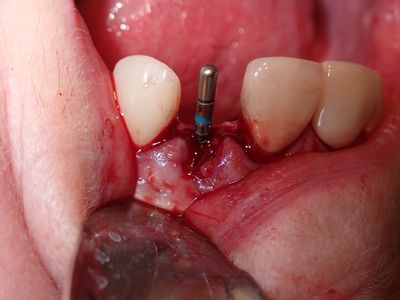

long root, atraumatic exo, loss of labial bone at apical end of socket, implant placed in ideal position, socket and buccal grafted with allograft and collagen membrane. Sutured prior to loading implant with screw-retained temp crown out of centric and protrusive occlusion

PA180026.JPG